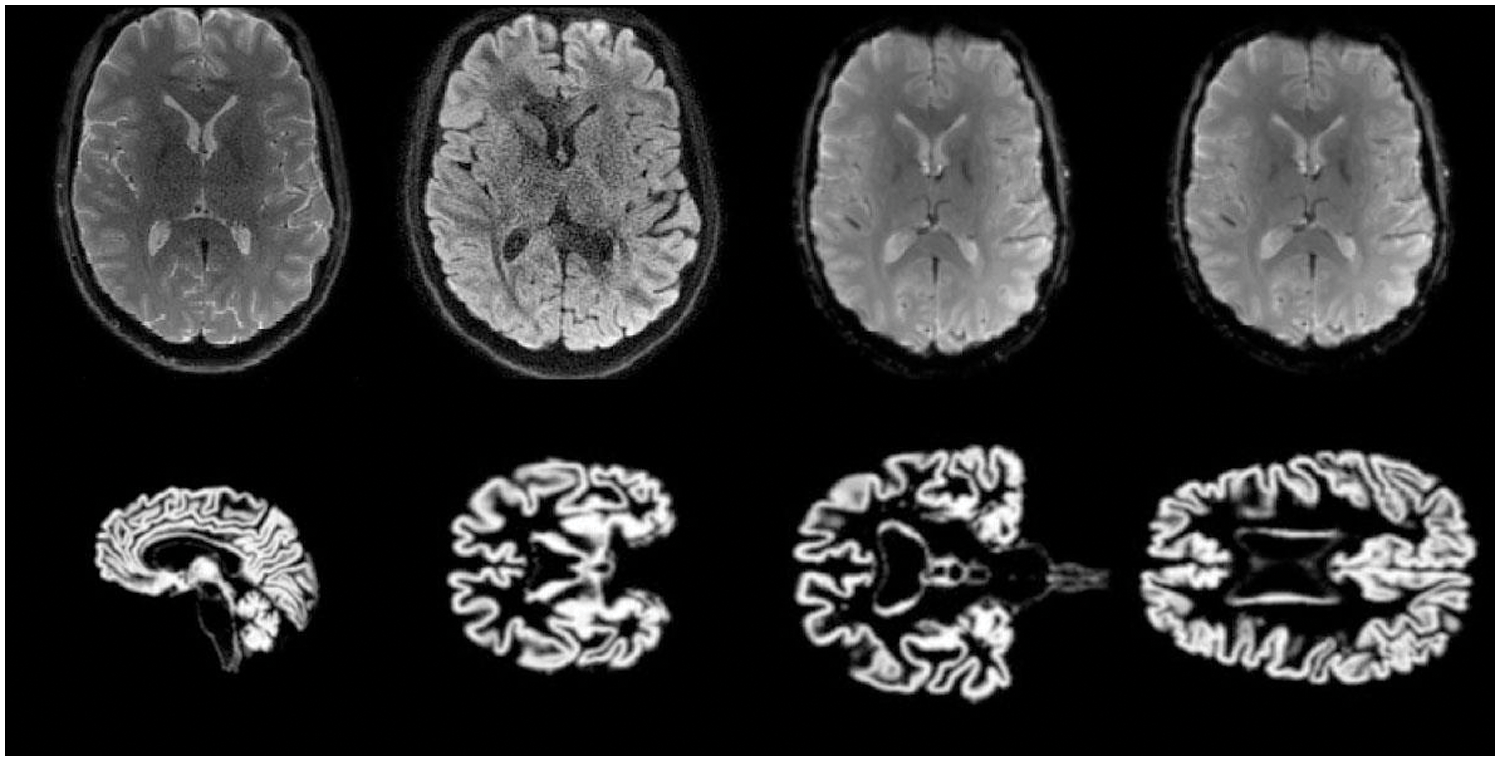

Our study employed the statistical parameter mapping SPM12 for pre-processing T1-weighted images in the neuroimaging informatics technology initiative (NIFTI) format. Full-brain segmentation was applied to obtain gray matter (GM), white matter (WM), and cerebrospinal fluid (CSF) images. Specifically, we utilized GM images for our proposed technique to diagnose individuals in the standard control (NC) and mild cognitive impairment (MCI) stages. We employ bias regularization in this stage with a judiciously chosen cutoff value of 0.0001. This regularization technique helps correct image artifacts and inconsistencies that might arise during data acquisition, ensuring that our analyses are based on accurate and reliable data. Additionally, we apply a full width at half maximum (FWHM) of 60 mm, which aids in smoothing the images, reducing noise, and enhancing the discernibility of relevant features. Affine regularization is another essential component of our pre-processing pipeline. We employ the widely recognized ICBM (International Consortium for Brain Mapping) space template to achieve this. This template provides a standardized reference frame that facilitates the alignment and normalization of brain scans across all datasets. Ensuring all images are registered to a common spatial framework mitigates potential variations in brain anatomy and size, thereby enabling meaningful comparisons and analyses.

Spatial normalization is conducted using the Montreal Neurological Institute (MNI) space, a widely adopted standard in neuroimaging research. The MNI space serves as a common coordinate system, allowing us to map brain structures and regions of interest across different subjects and studies precisely. This step is crucial for achieving consistency and accuracy in our analyses, particularly when dealing with diverse datasets. We apply a Gaussian kernel for image smoothing to further refine our data. This process helps to enhance the signal-to-noise ratio in our neuroimaging data, making it easier to detect and analyze subtle changes or patterns. The choice of kernel size and smoothing parameters is carefully considered to balance noise reduction and the preservation of essential features in the images. Some samples are shown in Fig. 1.

Figure 1: Training and testing MRI 2D-Images